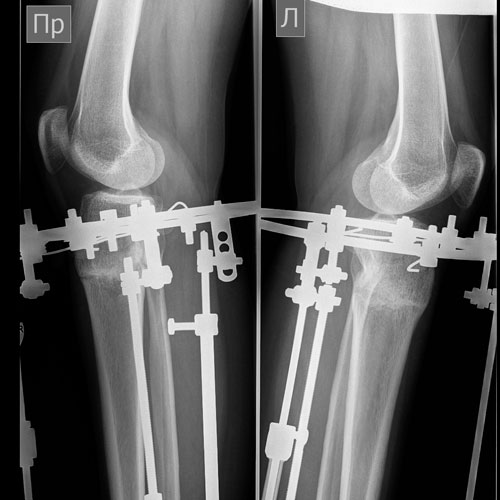

Дата операции 11.03.2014г.

Дата снятия аппаратов 10.06.2014г.

Срок лечения 3 месяца.